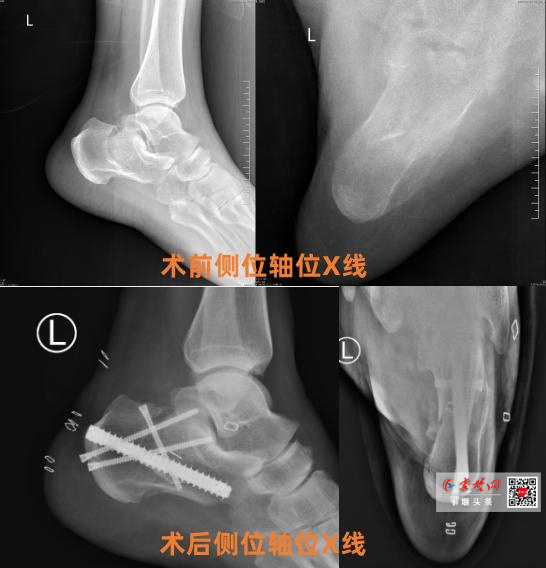

• 十堰人医应用“跟骨钉中钉”微创技术助骨折患者快速康复

十堰人医应用“跟骨钉中钉”微创技术助骨折患者快速康复

近日,十堰市人民医院创伤骨科1病区成功完成一例采用“跟骨钉中钉内固定系统”的微创手术,为51岁左跟骨粉碎性骨折患者左先生实施精准治疗。术后患者恢复进程显著优于传统术式,次日即下地行走,充分凸显了该技术的临床优势。患者左先…